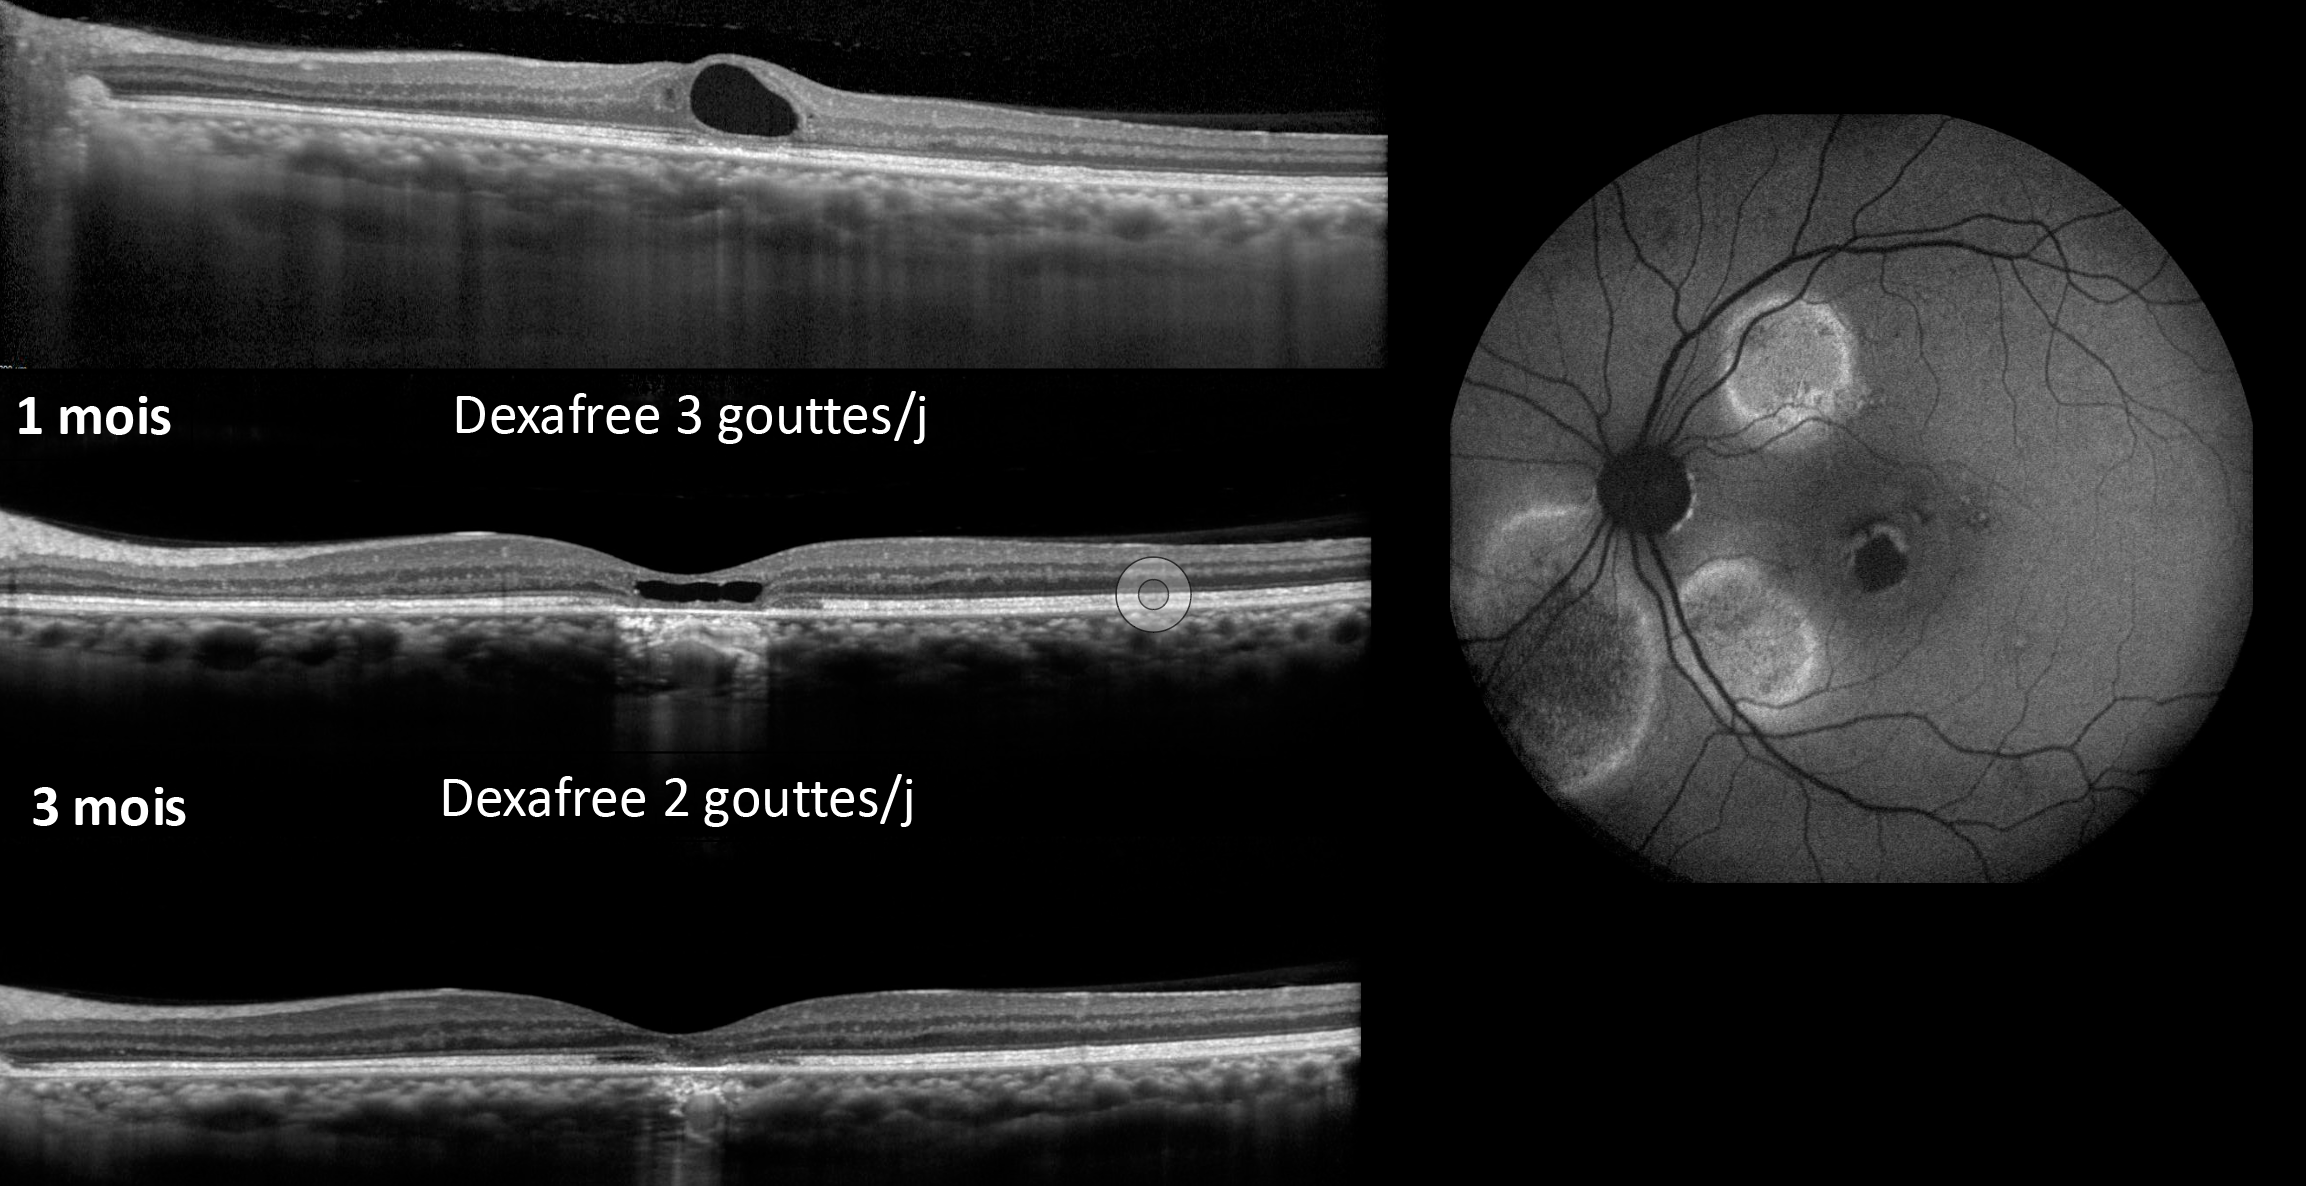

Figure 1. Évolution vers l’atrophie d’un néovaisseau de type 3. Bien que l’activité néovasculaire du néovaisseau soit bien maîtrisée avec le traitement, l’acuité visuelle a progressivement diminué à cause de l’atrophie sous-jacente.